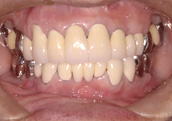

| こちらの症例は、歯がぐらぐらし噛めないということで来院されたケースです。

3ヶ月に一度の定期健診とクリーニングだけのために来院されています。ブラッシング指導・歯のクリーニングのみで来院され、今では、かたいものがなんでも噛め食事がおいしいと満足し、安定した状態で18年経過し今日に至っています。 この18年間、削ったり詰めたりという、従来考えられている歯科治療は全く行っていません。患者様と歯科衛生士の努力の結果です。この先もこの状態が保たれれば、将来的に歯を失うことなく入れ歯にならないと思われます。患者様が幸せになれば、私たちスタッフ一同も幸せです。 |